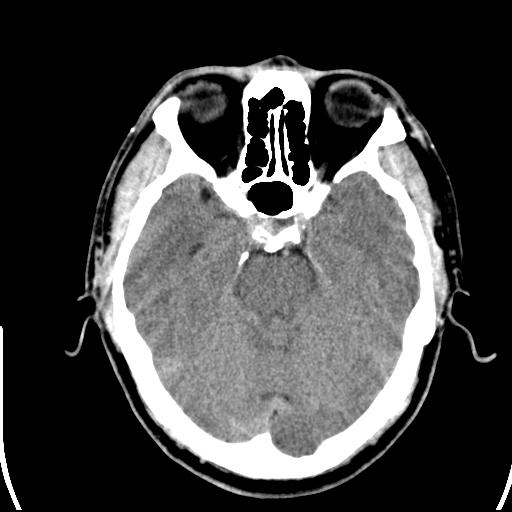

头皮下高密度结节影???临床上在老年男性比较常见。大家看看是什么?成因是? 本例患者,男性,51岁。外伤来诊。无染发史及发根植入史。

考虑异物。

皮下钙化点

没见过,可能为毛囊钙化。

考虑钙化。